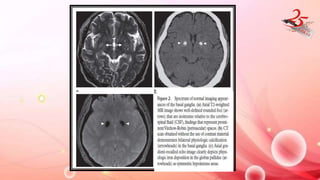

FAHR DISEASE

• Bilateral striopallidodentate calcinosis

• B/L symmetric deposition of Ca and other minerals in BG ,Thalamus

, Dentate nuclei and centrum semiovale in absence of

HYPOPARATHYROIDISM.

• CLINICAL FEATURES : Headache , vertigo , movt disorders , syncope ,

seizures , coma, dementia , parkinsonism , chorea, dystonia etc.

IMAGING FINDINGS:

• MRI/CT : B/l symmetric dense calcifications in BG , dentate nuclei ,

thalamus , subcortical white matter .

FAHR DISEASE • Bilateralstriopallidodentate calcinosis • B/L symmetric deposition of Ca and other minerals in BG ,Thalamus , Dentate nuclei and centrum semiovale in absence of HYPOPARATHYROIDISM. • CLINICAL FEATURES : Headache , vertigo , movt disorders , syncope , seizures , coma, dementia , parkinsonism , chorea, dystonia etc. IMAGING FINDINGS: • MRI/CT : B/l symmetric dense calcifications in BG , dentate nuclei , thalamus , subcortical white matter .